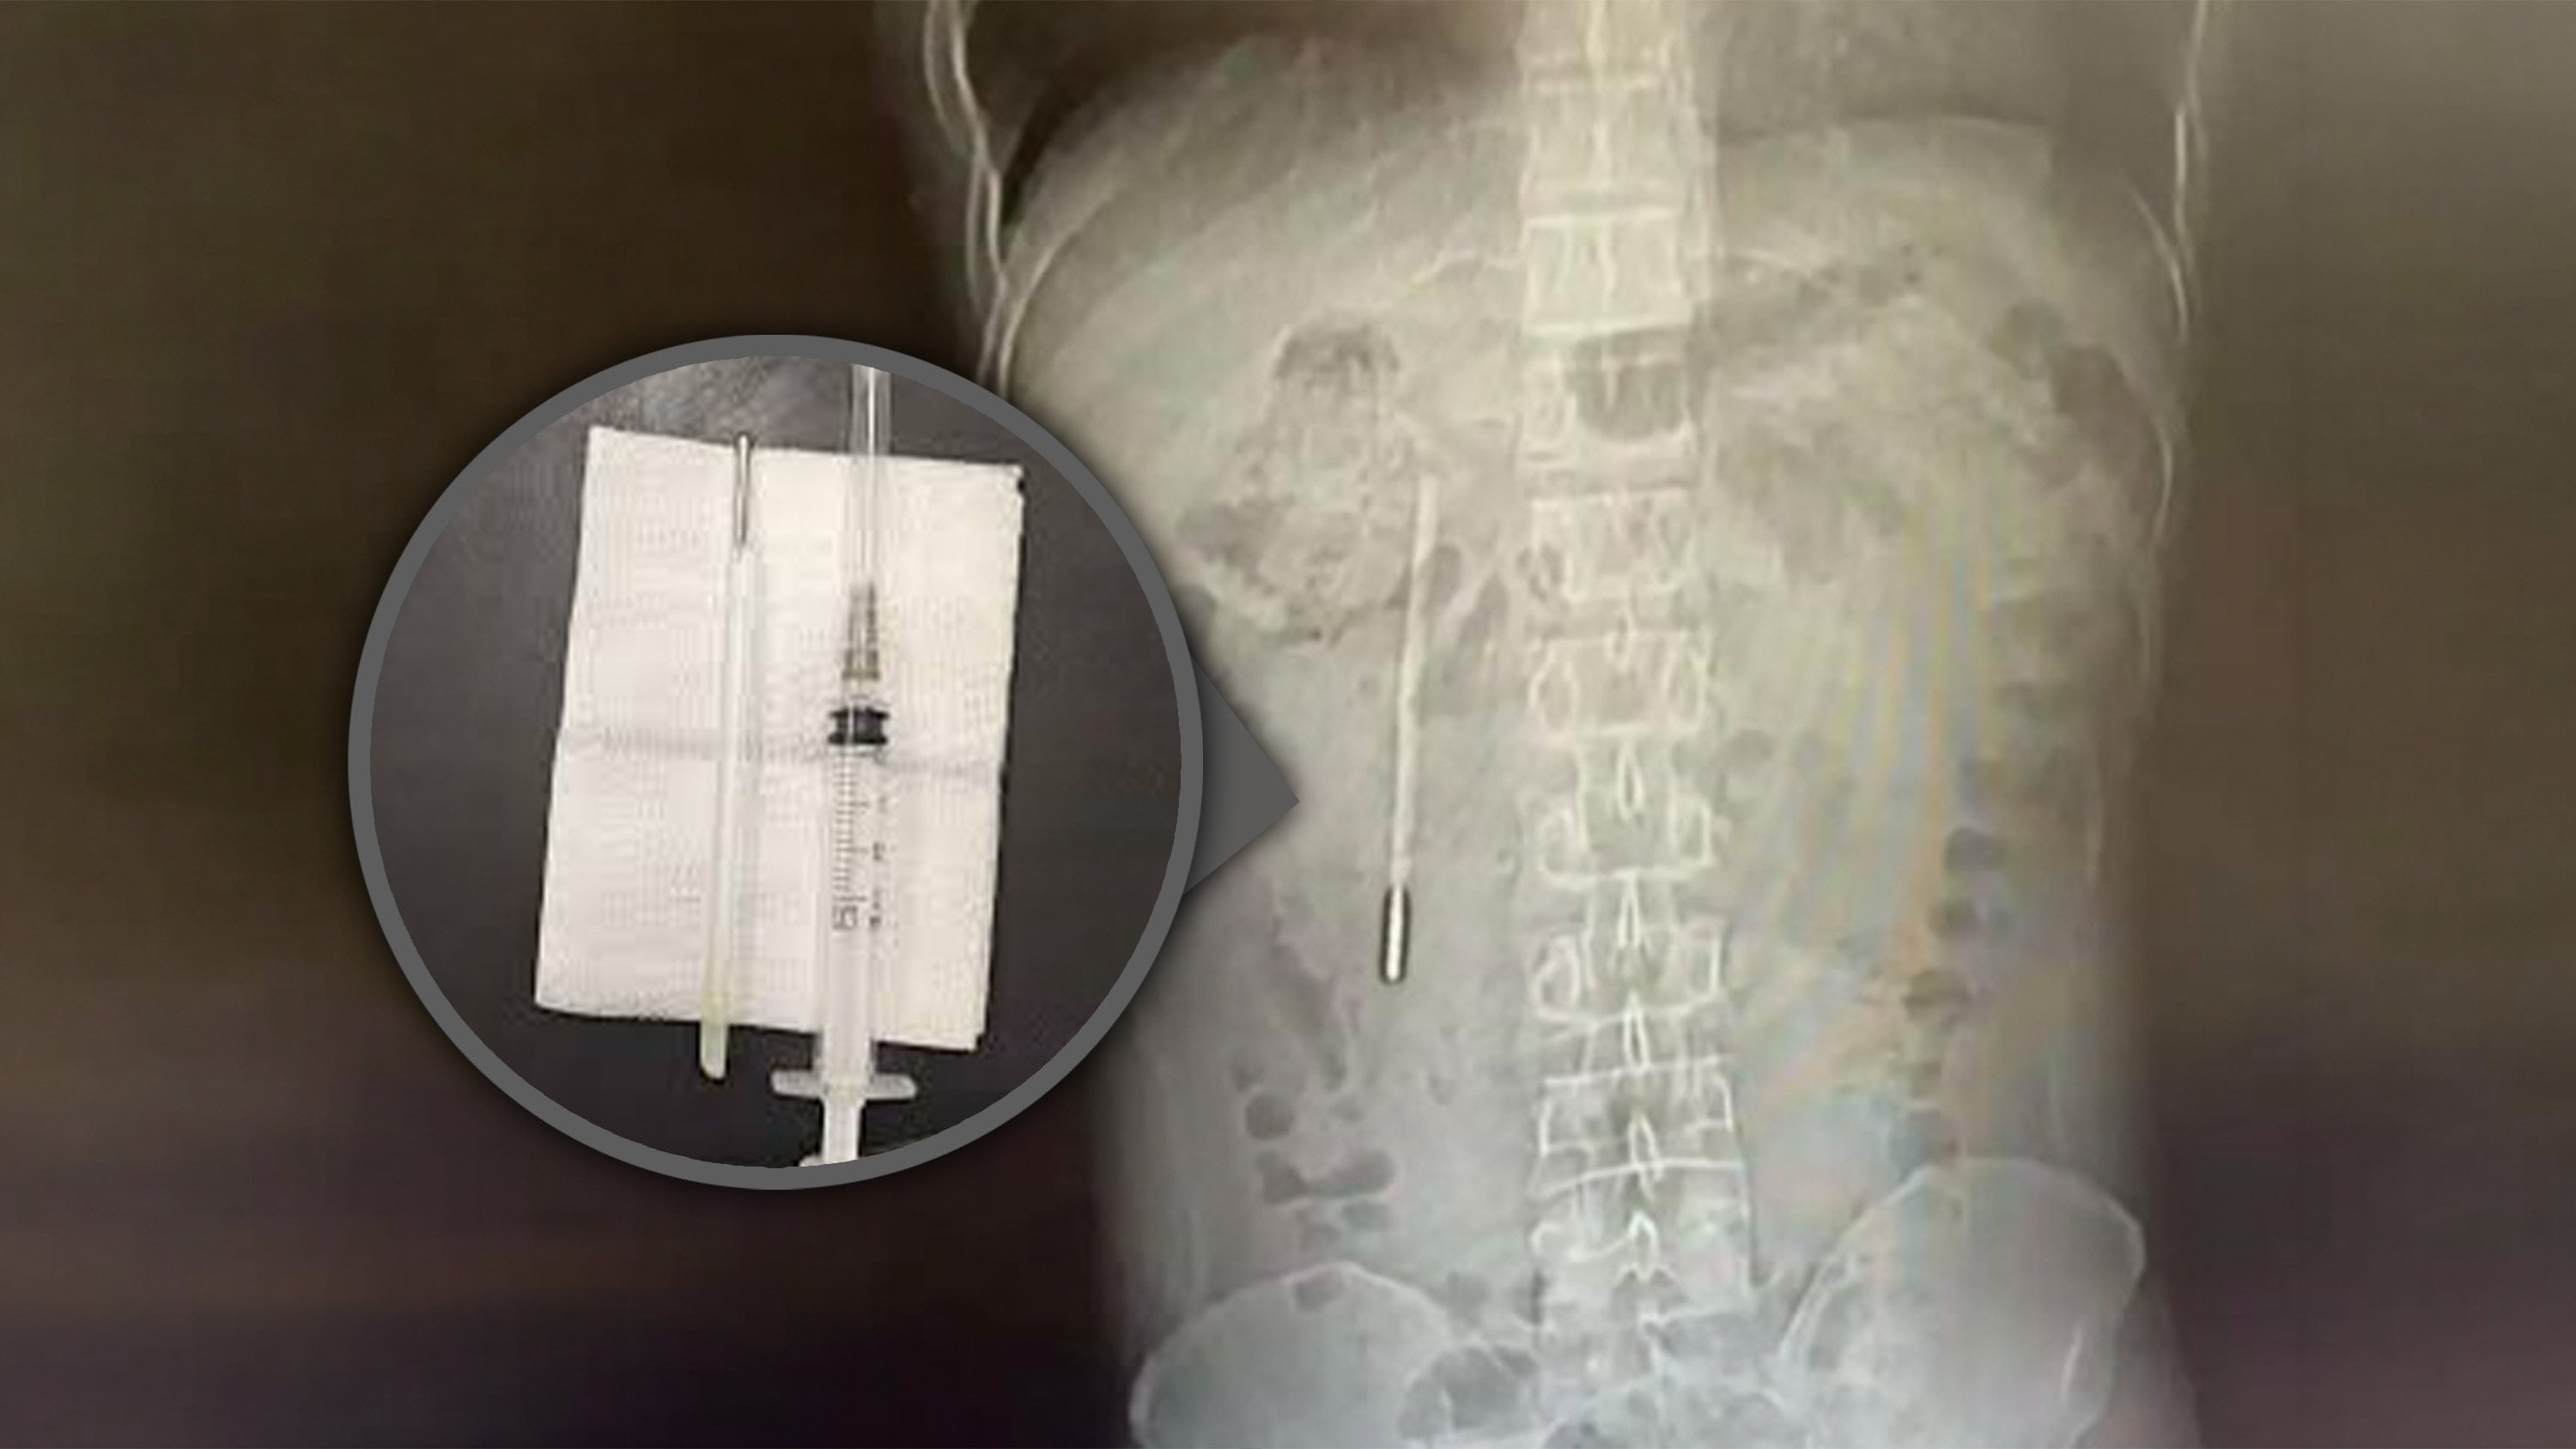

Chinese man with stomach pain finds thermometer swallowed as child still inside him

Surgeons perform emergency operation to remove offending object; extracted device remains intact but temperature measurements had faded.